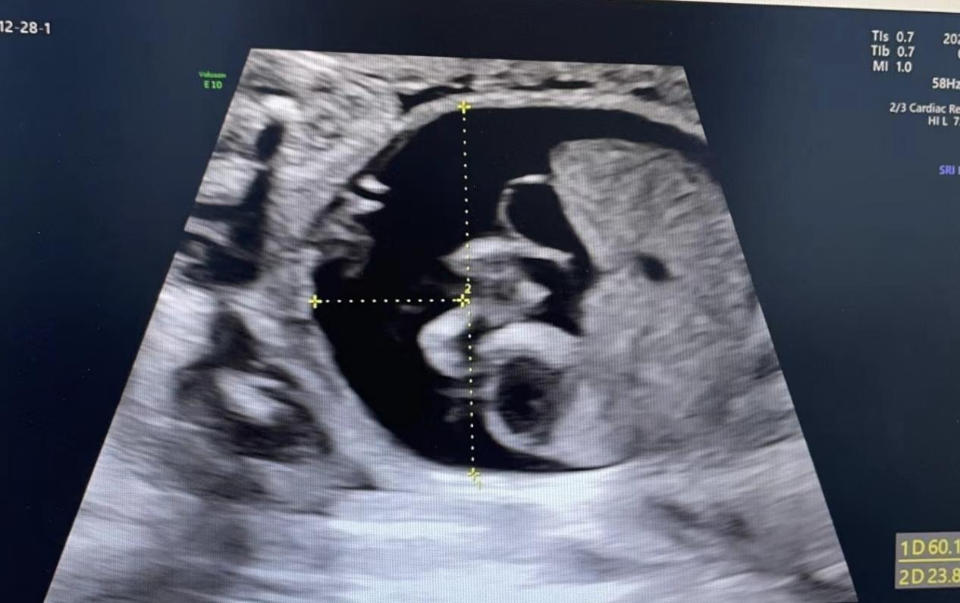

王谢桐立即牵头的胎儿医学团队立即组织了包括超声科、输血科、新生儿科等相关学科的多学科联合会诊,决定通过胎儿宫内输血进行抢救治疗。“由于胎儿水肿,首次输血采用半量输血,成功避免了输血并发症。”王谢桐说,随后陆续进行了3次宫内输血,输血后胎儿大脑中动脉收缩期峰值流速下降,水肿明显改善。

胎儿贫血导致血流黏稠度下降、胎儿脑保护及心脏输出量增加,作为胎儿大脑的主要供应血管大脑中动脉的血流速度会明显加快,预测胎儿贫血的敏感度和特异度很高。王谢桐讲道,如果胎儿大脑中动脉血流峰速(MCA-PSV)>1.5 MoM,尤其检测到胎儿积液或水肿征象,高度怀疑胎儿重度贫血,需要脐血穿刺胎儿血液检查确定有无贫血,并进行胎儿输血的相关检查。